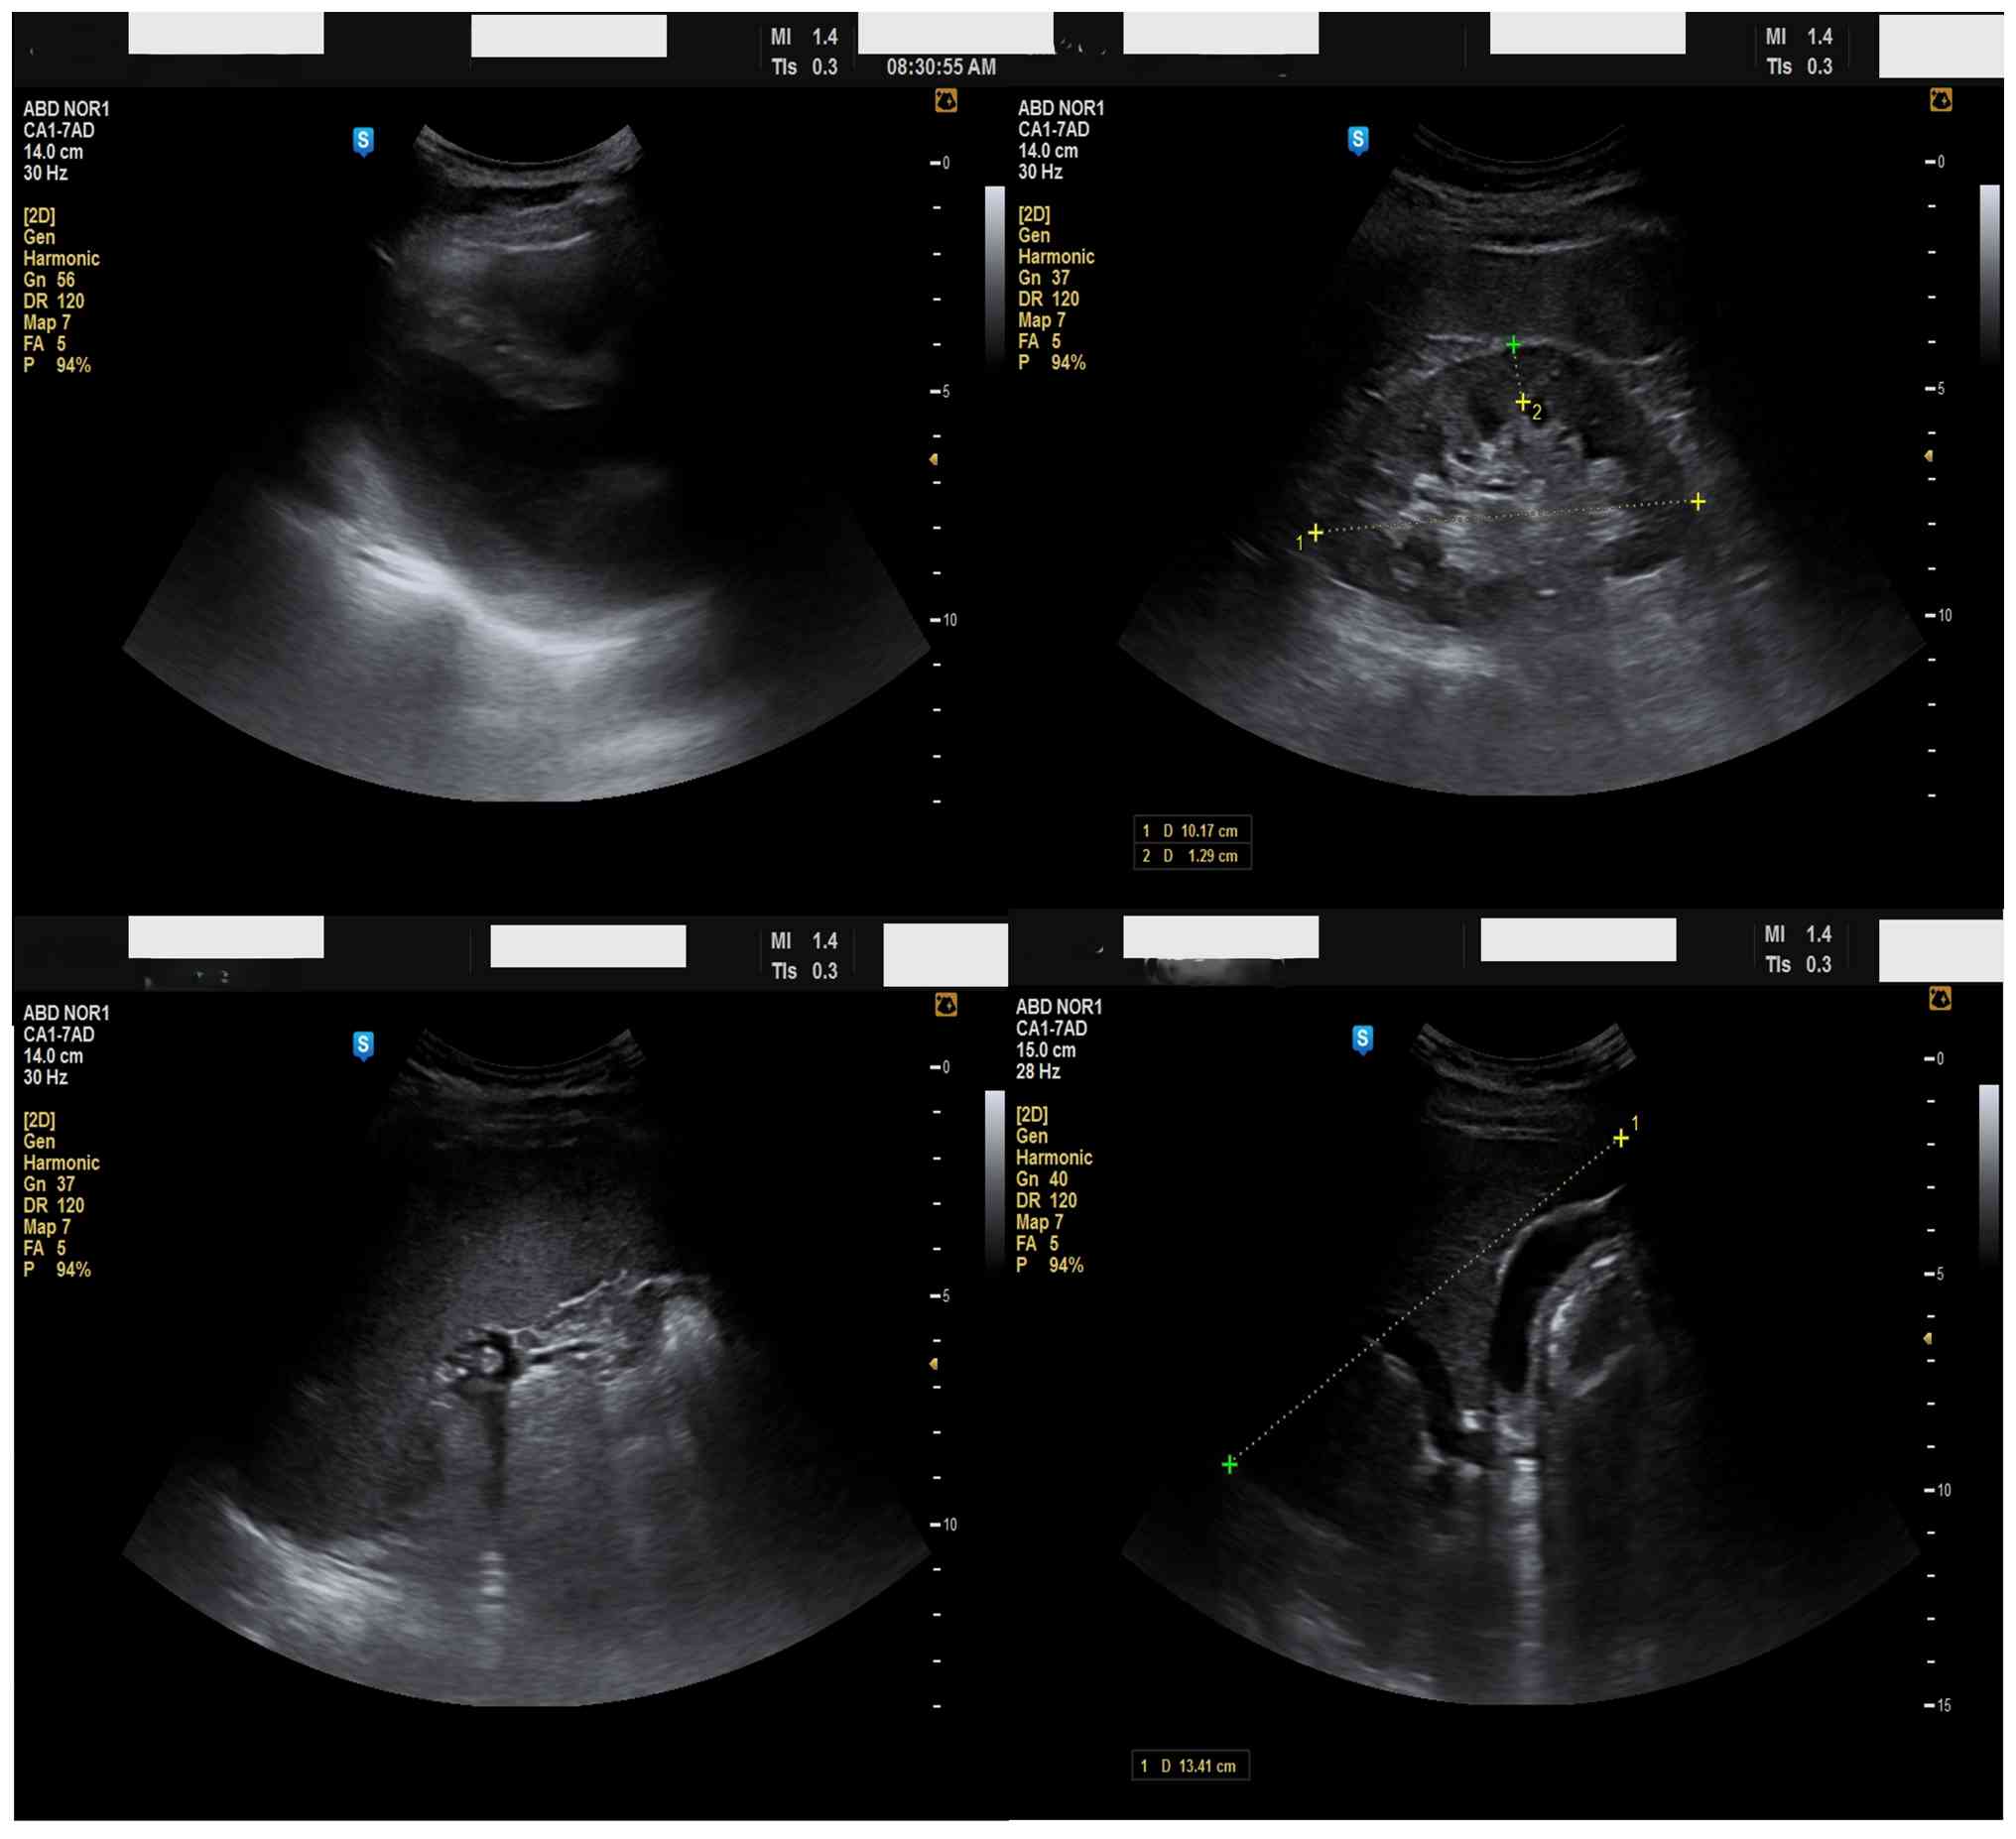

An electrocardiogram revealed sinus rhythm with right axis deviation, a negative QRS complex in Lead 1, and inverted P and T waves in Lead 1, with a progressively decreasing R-wave amplitude from V1 to V6. A chest X-ray demonstrated a right-sided cardiac shadow consistent with dextrocardia (Fig. 1). An electrocardiogram revealed sinus rhythm with right axis deviation, a negative QRS complex in Lead 1, and inverted P and T waves in Lead 1, with a progressively decreasing R-wave amplitude from V1 to V6 (Fig. 2). Ultrasonography showed the spleen on the right (Fig. 3) (splenomegaly 14.5 cm), with normal kidneys, consistent with situs inversus totalis.

Abdominal ultrasonography showing the

spleen in the right hypochondrium.

Figure 3

Abdominal ultrasonography showing the spleen in the right hypochondrium.